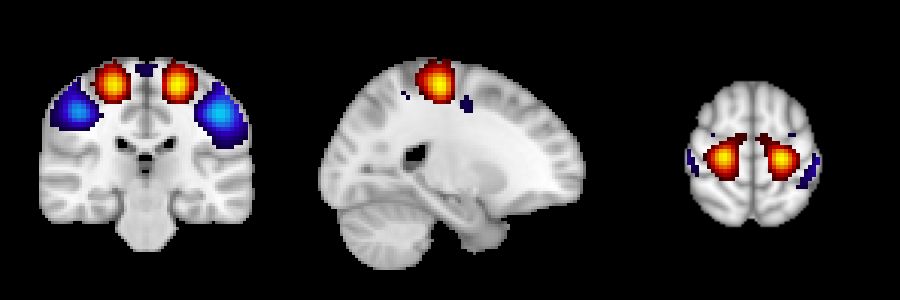

Output example